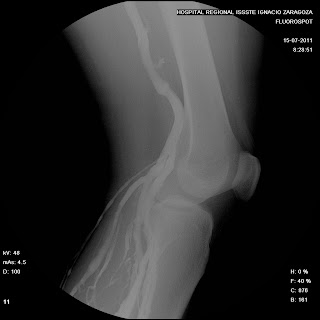

žA continuacion se centra la rodilla y se toma Rx de rodilla AP con la ligadura inferior aun colocada y otra sin ella .

žFinalmente se toma una incidencia lateral u oblicua de rodilla